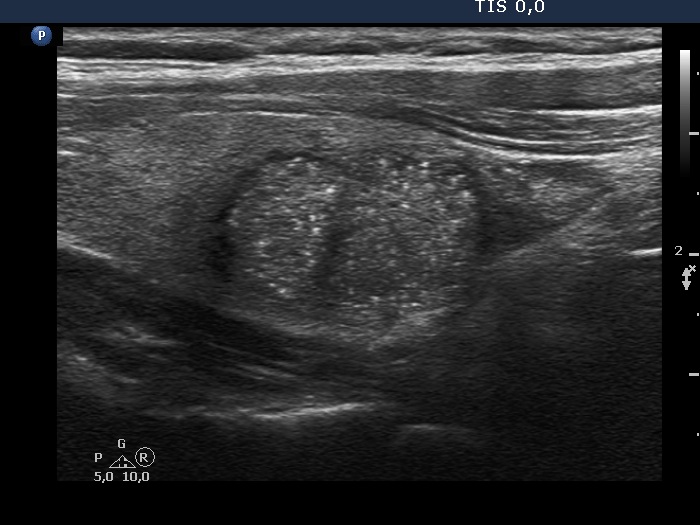

Ultrasonography. The thyroid was echonormal. There was a hypoechogenic nodule in the right lobe. The nodule had numerous punctate echogenic granules.

The echogenic figures are very difficult not to interpret as microcalcifications. Nevertheless, thorough analysis reveals that some of the bright granules has a short tale, and great proportion of these figures are related to ventral tiny hypoechoic areas, probably cysts. Moreover, there are not only echogenic granules but also short echogenic lines within the nodule. Taking all in all, these echogenic figures are very suspicious being microcalcifications.

- The ACR TIRADS is the only one which does not use the term 'microcalcification', instead they use the term 'punctate echogenic foci', which includes microcalcifications and short-tail comet-tail artifact. This example stands for the advantage of the ACR terminology.

- In such nodules it is to be considered to delay the ultrasound report till the result of FNA. In this patient FNA disclosed benign colloid goiter and there were macrophages on the smear. The latter proved that the nodule had cystic areas. If we take this fact into account, than it can solve our concern about the interpretation of echogenic granules.